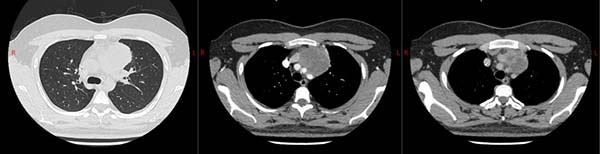

23 岁广东小伙小伟半年前出现胸闷、胸痛症状,在当地检查发现了前纵隔肿物,外院穿刺怀疑是恶性程度较高的卵黄囊瘤,但经过 7 次化疗却效果不佳,多家医院都因手术风险较大不敢接手。检查显示,这个 7×6 厘米的肿物紧紧 “扒” 着主动脉弓、肺动脉干等重要大血管,甚至可能侵犯了心包和左上肺,如同在心脏和大血管旁 “埋雷”。

刘志东团队为他制定了 “组合拳” 方案,在2025 年 7 月 3 日,通过正中开胸手术,完整切除纵隔肿物和胸腺,并精准处理了受侵犯的左无名静脉、左膈神经和左上肺部分组织,同时清扫了周围淋巴结。术后患者顺利脱机拔管,目前在普通病房恢复良好。